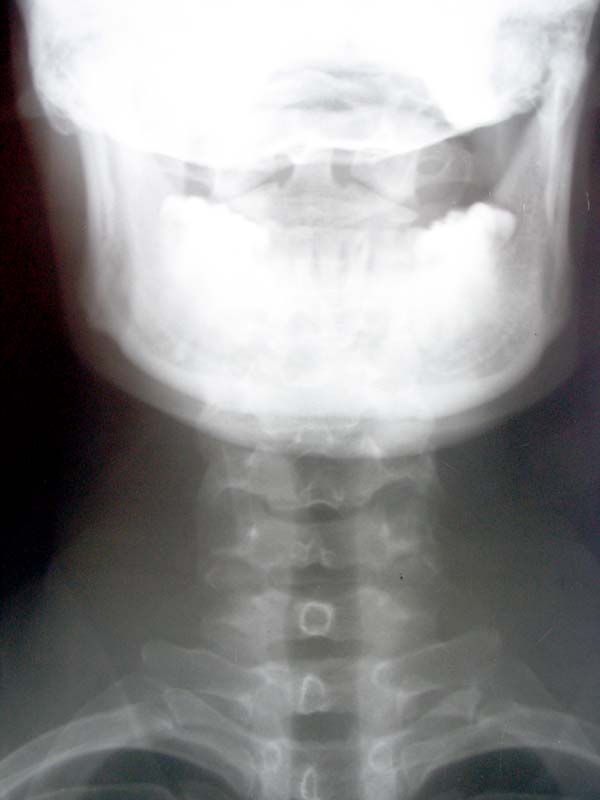

男,40y,颈部胀痛2天。

侧位片所示圈子内我认为还是投照体位所致,各解剖结构还是完好存在.正位片示环椎双侧块圆孔样改变,应为变异,是侧方骨桥形成